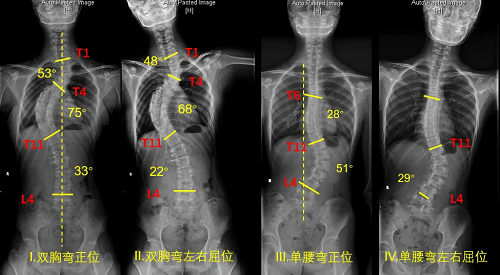

典型病例